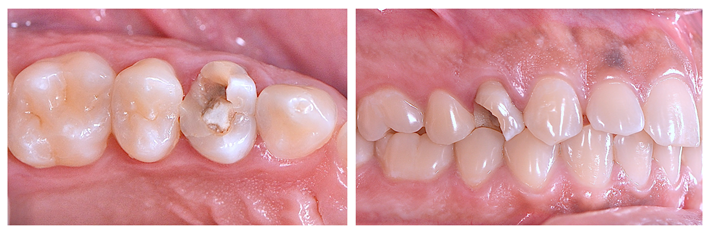

Paciente jovem (32 anos) apresentou-se na clínica com o primeiro pré-molar superior direito com fratura corono-radicular e grande lesão periapical com rompimento da cortical vestibular, sendo, portanto, indicada a extração dentária. Dada a idade do paciente e a importância de se manter a estética e a função na região, optou-se pela instalação imediata de implante dentário associada à preservação e regeneração alveolar.

Após o diagnóstico e planejamento, baseados em exames radiográficos e clínicos (Figuras 1 e 2), a primeira etapa foi realizar uma extração dentária atraumática (secção dentária e utilização de periótomo fino e flexível), visando a preservação completa do periodonto de sustentação. Após a curetagem para remoção total da lesão periapical, fez-se a instalação do implante alcançando-se um ótimo travamento inicial e um correto posicionamento ápico/coronal e tridimensional (Figura 3). O Túnel Check, da Implacil De Bortoli (Figura 4), foi utilizado para avaliar o posicionamento tridimensional do implante e selecionar a altura correta do cicatrizador – optou-se por um cicatrizador ao invés do parafuso de cobertura do implante para que não houvesse formação óssea sobre o parafuso, o que tornaria a reabertura muito mais traumática. Após, a membrana Cytoplast TXT 200 Singles (Implacil De Bortoli) foi personalizada e instalada inicialmente na face palatina (Figura 5 – ela não deve ficar tocando nas faces proximais dos dentes vizinhos), seguido do preenchimento alveolar (Figura 6) com substituto ósseo natural contendo 25% de colágeno, o Extra Graft XG-13 (Implacil De Bortoli). Por conter colágeno na sua composição, o Extra Graft XG-13 não fica liberando as partículas ósseas ao longo do processo de osteointegração.